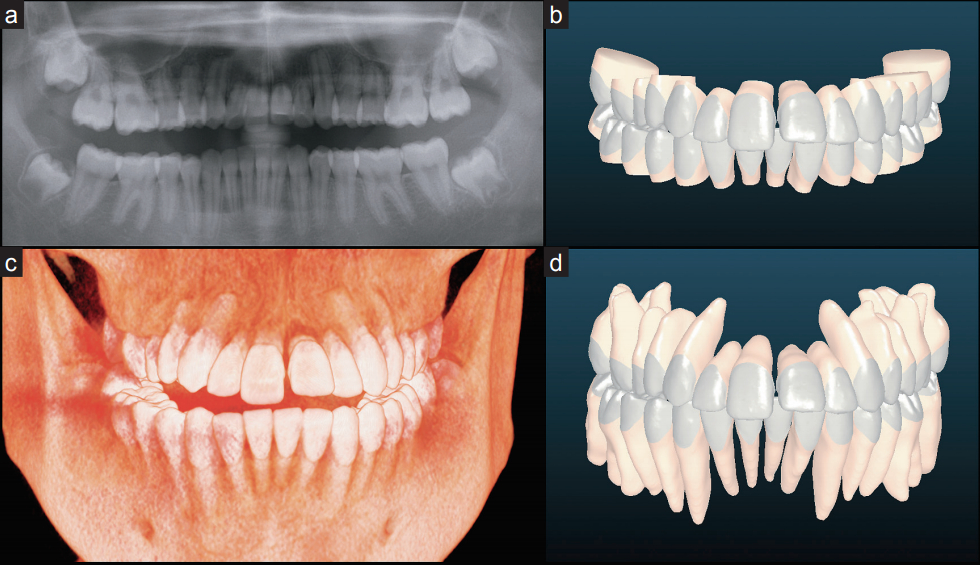

作为其中的重点技术——麦芽MAC数字化精确正畸,应用数字诊断技术,数字化全景片成像、数字化3D口扫取模、数字化3D正畸方案设计、正畸过程3D动画预览、3D隐形牙套及托槽打印等国际化新技术,新方法,实现牙齿向目标位置移动的精确控制,减少复诊次数和缩短近30%矫治时间,全面提升了口腔正畸的精确性和舒适性,为歪牙朋友带来全新的矫牙体验。

麦芽MAC数字化精确正畸不同于传统正畸方式,它是医生根据数字化诊断设计、基于患者个体情况,确定的全套个性化正畸诊疗方案,具备更舒适、更精确、更高效的牙齿矫正体验。麦芽MAC数字化精确正畸采用的个性化矫治器是由计算机程序根据个人口内数据精密设计而成,精确度更高,矫牙时牙齿移动的误差更小,可以加快你的矫正速度。由于它是完全贴合牙齿设计,舒适度会更高。在麦芽MAC数字化精确正畸过程中,医生还可以通过口内扫描定期监控你的牙齿移动状态,传统的矫牙方式只能通过肉眼看到牙冠的移动,而麦芽MAC数字化精确正畸则可以达到牙冠和牙根移动的精确控制,避免矫正过程中只移动了牙冠,牙根未移动而导致的反弹。